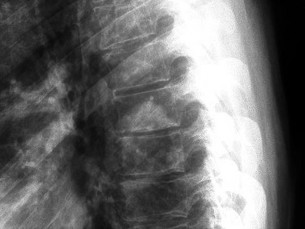

A 45-year-old male presents with severe right arm pain radiating down to his middle finger. Neurologic examination reveals prominent triceps weakness and an absent triceps deep tendon reflex. His biceps and brachioradialis reflexes are intact. MRI reveals a posterolateral cervical disc herniation. At which cervical spinal level is the pathology most likely located?

Explanation

The clinical presentation (triceps weakness, absent triceps reflex, and sensory symptoms radiating to the middle finger) is the classic triad of a C7 radiculopathy. The C7 nerve root exits the cervical spine through the C6-C7 neural foramen, making a C6-C7 posterolateral disc herniation the most likely structural cause.